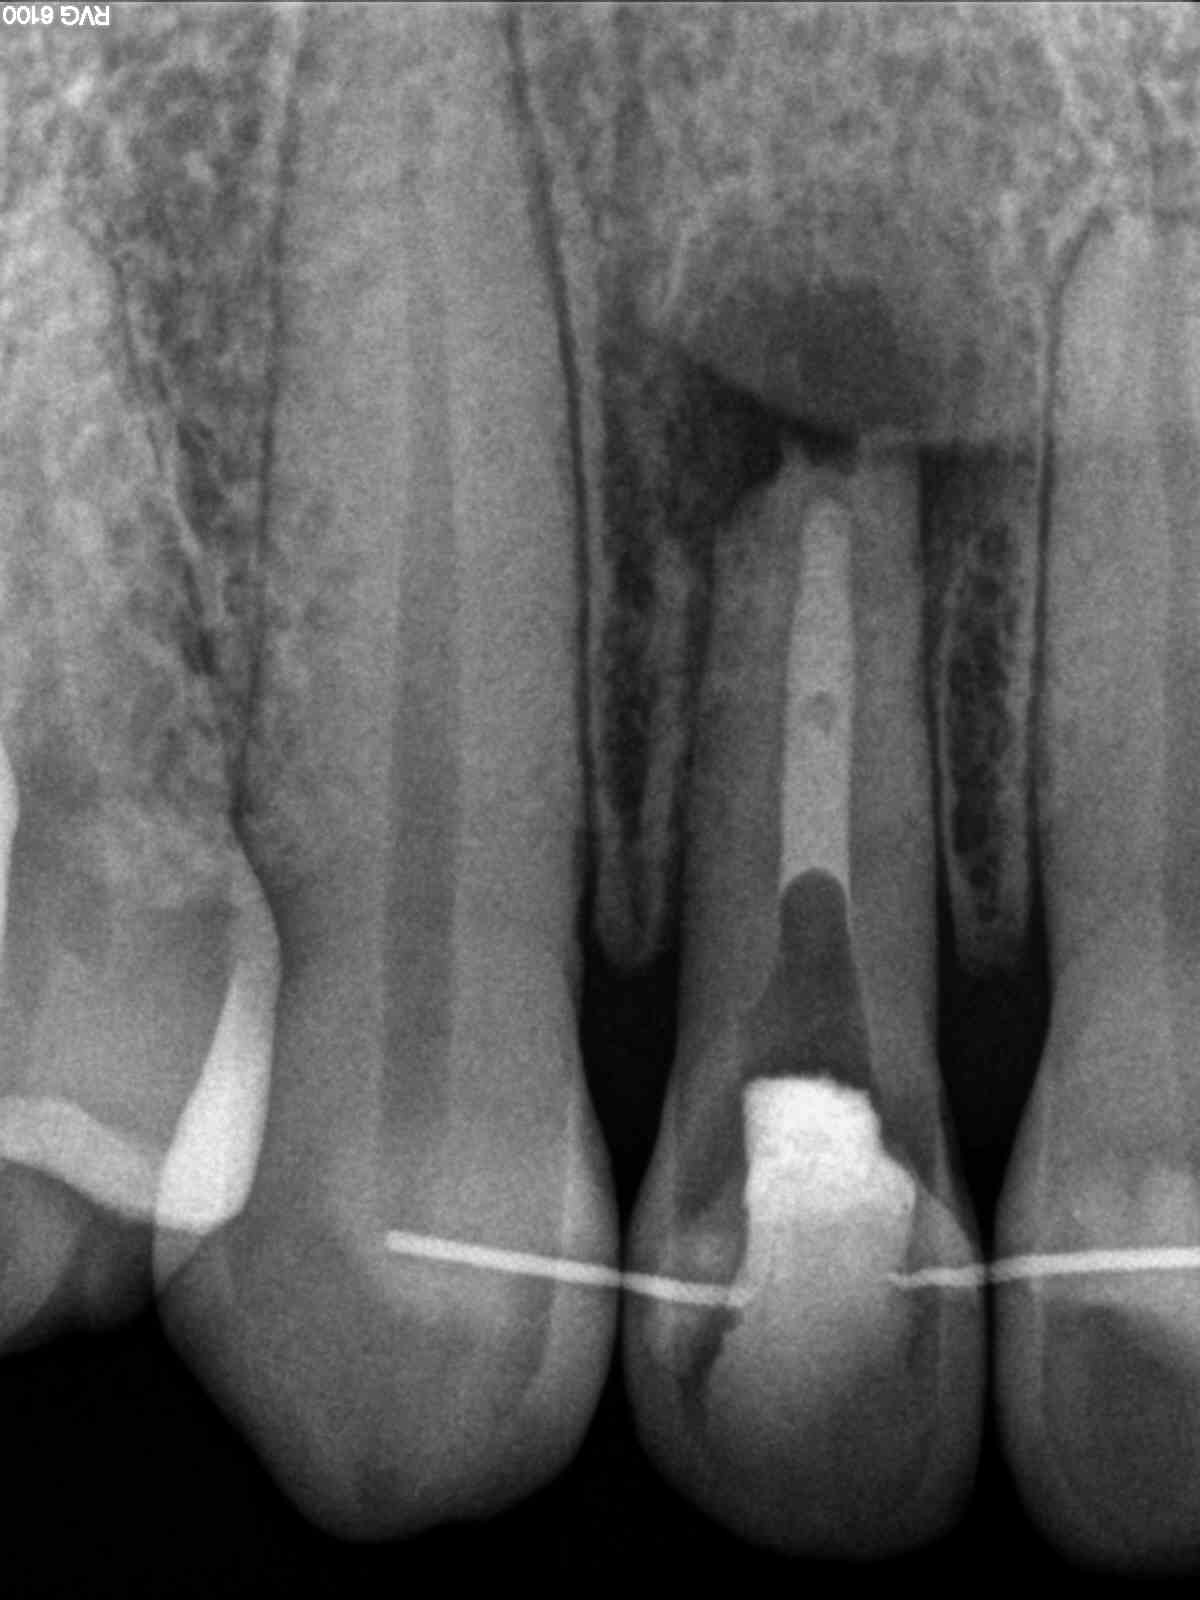

R3

1200 × 1600

As time goes by!